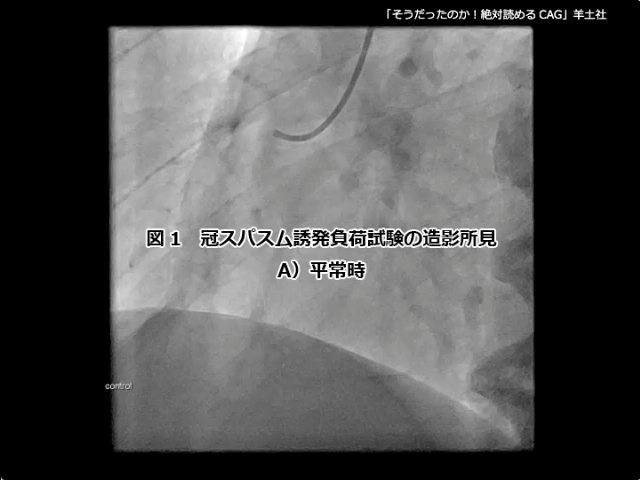

第5章-1 急性冠症候群の造影所見